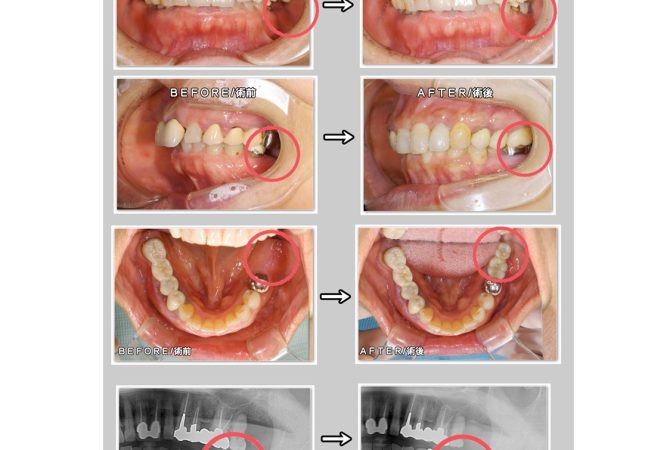

2026.2.9 症例 インプラントの症例 GBR法/骨補填材使用 詳しく見る 2026.1.13 学び インプラント学会の試験受験★ 詳しく見る 2025.12.27 症例 インプラントの症例 詳しく見る 2025.12.13 学び インプラント学会の予備試験受験&インプラント周囲炎の治療セミナー参加☆ 詳しく見る 2025.11.30 症例 インプラントの症例 GBR法/骨補填材使用 詳しく見る 2025.11.20 院内のこと インプラント手術 詳しく見る 2025.11.1 症例 インプラントの症例 GBR法/骨補填材使用 詳しく見る 2025.10.31 学び インプラント のための骨造成セミナーを受講 詳しく見る 2025.10.7 学び インプラント のセミナーに参加してきました 詳しく見る 1 / 3 ページ23次へ »